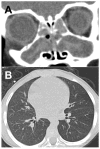

Background: People with cystic fibrosis (CF) sinus disease have developmental sinus abnormalities with airway bacterial infection, inflammation, impaired mucociliary clearance and thick obstructive mucus. The pathophysiology of airway disease in CF is not completely understood, and current treatments in CF sinus disease ameliorate symptoms but do not provide a cure.